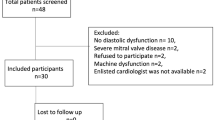

Study population

Patients scheduled for non-cardiac surgery were included in this study. The inclusion criteria were: a) Low-risk (ASA I-II) elective surgery, b) surgery planned to be performed under total intravenous anaesthesia and positive pressure ventilation and c) informed consent was obtained. Exclusion criteria were: a) history or clinical or laboratory signs of cardiac, pulmonary or systemic disease, b) any cardiac or antihypertensive medication, c) abnormal ECG d) age < 18 year and e) a body mass index ≥30 kg m− 2.

Experimental protocol

The intra-observer agreement of RV free wall strain and LV global longitudinal strain were assessed by the coefficients of variation for paired observations of RV and LV strain from the measurements of the first (baseline) examination. Our data were normally distributed and expressed as mean ± SD. To detect a difference in LV GLS of 1.5% units, 17 patients were needed to be included at a standard deviation of the mean differences of paired measurements of 2. Paired t-test was used to compare the means before and after induction of anaesthesia. A probability level (p-value) of less than 0.05 was considered to indicate statistical significance. Statistical analysis was performed using SPSS for Mac version 21.

Twenty-one patients were included in the study, 11 male and 10 females with a mean age of 47 ± 15 years (Table 1). Data on the doses of propofol and remifentanil and the ventilatory settings are shown in Table 1. The bispectral index (BIS) was used to determine the anaesthetic depth [20]. The BIS level was 39 ± 9 after induction of anaesthesia. A BIS value between 40 and 60 is considered to be an appropriate level for general anaesthesia.